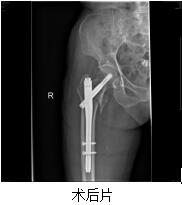

患者林某某,女性,100岁,秀屿区东峤镇人,于2016-08-30在家摔倒,右髋部疼痛伴活动受限,不能站立及行走。于2016-08-31求诊我院,急诊拟“右股骨转子间骨折”收住我院。患者既往有高血压病、心脏病、慢支、肺气肿等病史。患者入院后,医院领导高度重视,组织心血管内科、呼吸内科、麻醉科等相关科室全院大会诊,并制定详细周密的诊疗计划,决定予以行薇创骨折内固定术。完善相关术前准备后,于2016-09-02在麻醉下行右股骨转子间骨折闭合复位PFNA内固定手术治疗。手术时间才50分钟左右,手术过程顺利,术中出血少。术后di1天,患者右髋部疼痛已缓解明显,可以自行床上翻身、坐起来,术后12天,患者康覆出院,成效满意。

总之,老年人一旦摔倒出现髋部疼痛,千万不要扶起站立,更不能行走,应咨询骨科医生,或行必要的相关检查(如拍片等),以防止进一步加重损伤。如为股骨转子间骨折,闭合复位PFNA内固定具有薇创(切口小)、出血少、创伤小、好的快等优点,术后就可以早期床上活动双下肢,骨折愈合后能下地较好,即便不能下地,在病床上活动也很好,就可以明显降低老年人转子间骨折的死亡率,重新下地走路也不再是单纯的梦想!骨科又一次为百岁老人成功完成骨折手术,再一次体现了我院的综合实力!